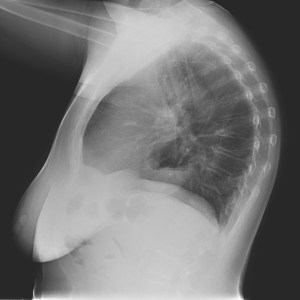

Otro caso:

Mujer 64 años. Preoperatorio

No olvidar aplicar la sistemática.